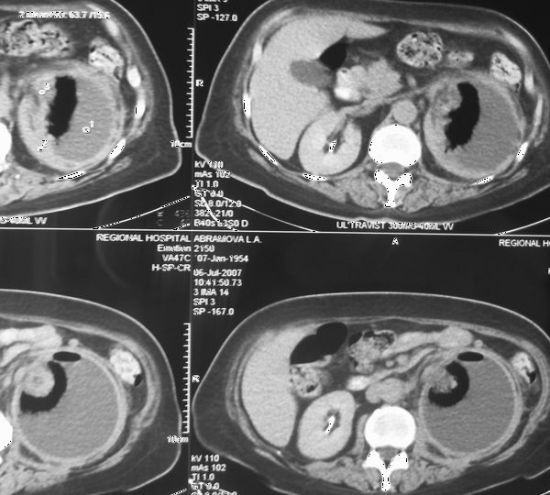

Абсцесс почки